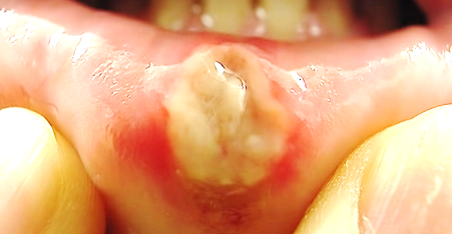

◈ 구내염이란?

세균이나 바이러스로 생기는 염증인데 입안 세균과는 관련이 없습니다.

구내염에 걸리면 피부의 상피세포가 파괴됩니다.

속살에 입속의 세균들이 2차 감염을 일으켜 염증이 심해집니다.